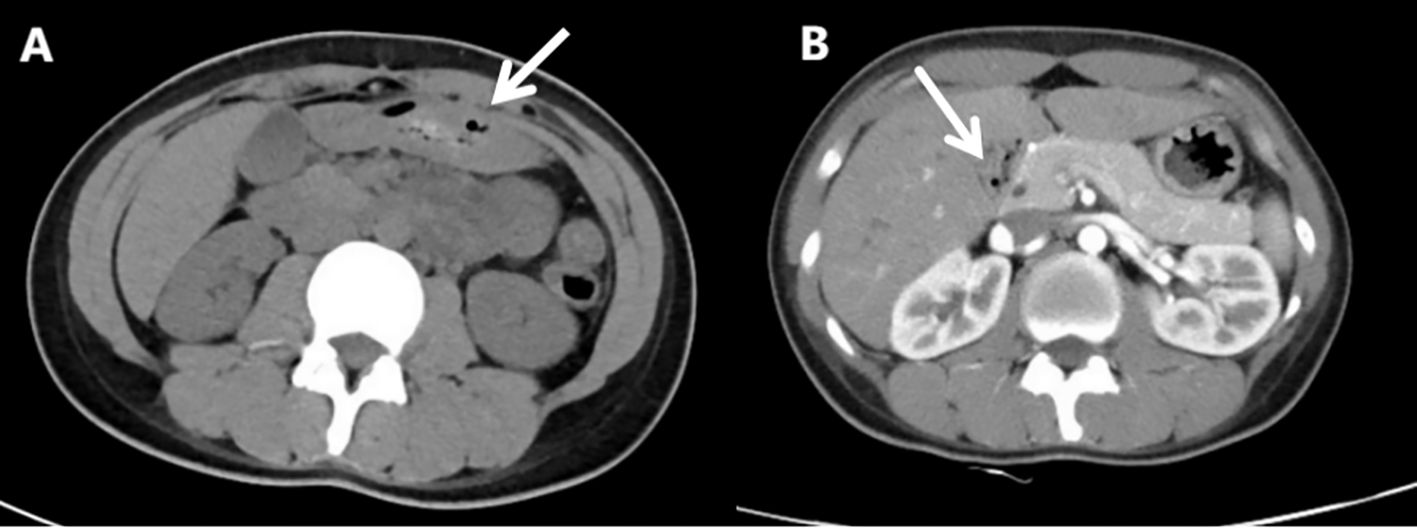

After admission to the Department of Gastroenterology, further workup revealed decreased complement C3 (0.29 g/L) and C4 (0.05 g/L), elevated total IgE (161.80 IU/mL), and positive autoantibodies including ANA, anti-histone, anti-nucleosome, anti-Ro-52, anti-SSA, anti-ssDNA, and anti-dsDNA antibodies. These findings supported systemic autoimmunity rather than isolated urticarial vasculitis. Reviewing her past history, it was found that she had urticaria attack one month ago. Reexamination CT showed that there was a moderate amount of ascites (Figure 2A), and her horizontal duodenum, jejunum and proximal ileum showed extensive edema and thickening (target ring sign) (Figure 2B).

Figure 2. Re-examination of abdominal computed tomography scan(Aug 31st, 2024). (A) Moderate ascites. (B) Widespread edema and thickening of the intestinal wall in the horizontal segment of the duodenum, the entire segment of the jejunum, and the proximal segment of the ileum (target ring sign).